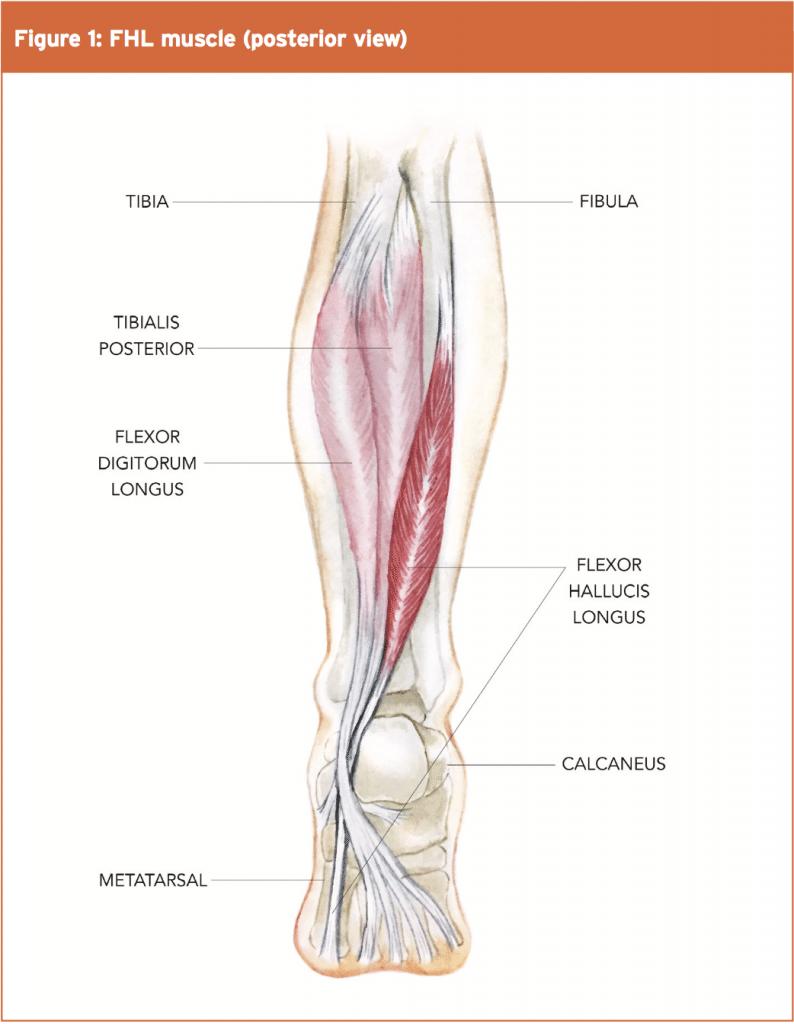

(1)急性足底过度屈曲损伤和(2)慢性重复性微创伤。这两种机制的相似之处在于后部软组织,后者可能在距骨后和跟骨之间继发性肥大和压缩。骨体的存在(距后三角骨(OT)和Stieda突)会进一步缩小这个空间,这导致了它的另一个名称“距后三角骨综合征”(图12)。51这种增生的压迫导致区域肌腱和韧带的损伤。拇长屈肌腱鞘炎通常受累(图12)。重要的细分包括跟腱肌病/撕裂、关节病、急性距骨后突骨折、拇长屈肌腱鞘炎、Haglund综合征、骨软骨损伤和跟骨后滑囊炎。

图12。

后踝关节撞击的侧位矢状位图示:(a)足底弯曲的踝关节伴有相关的os三角,后软组织被卡压,包括距骨后韧带(PTFL)和相关的滑膜炎。(b) 由于两者关系密切,刺激和增厚的屈肌支持带可引起长屈肌肌腱刺激和腱鞘炎。